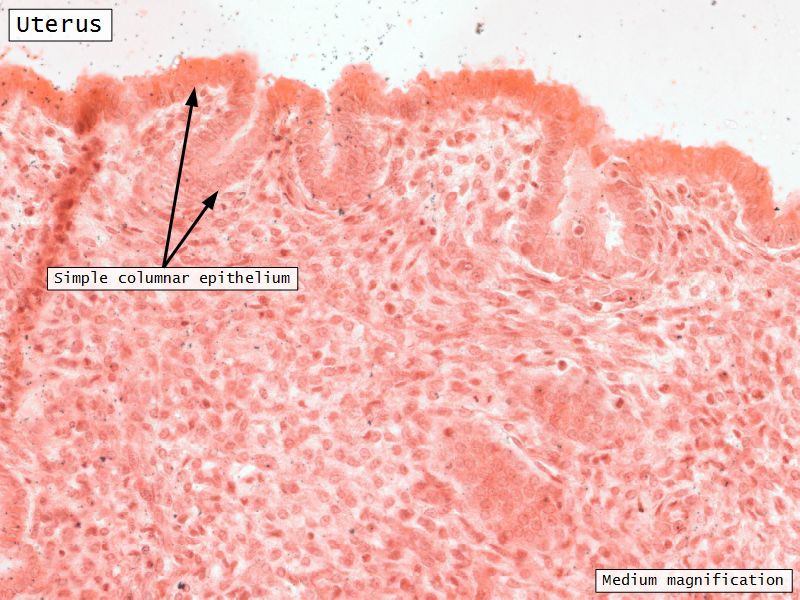

Uterus

Uterus

3 regions3 layers

Three layers

- Endometrium

Endometrium

Endometrium

- Epithelium

- Simple columnar

- Two cell types

- Secretory

- Ciliated

- Glands

- Similar but fewer ciliated